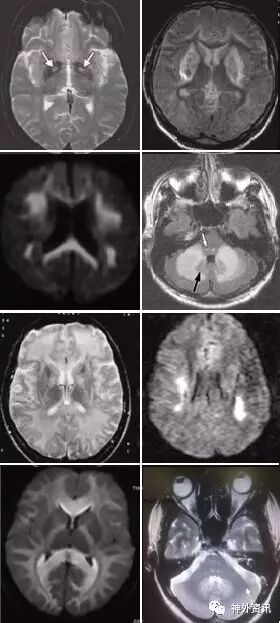

(重要申明:以下每个部分会配磁共振图片,因疾病和影像之间存在同病异象、同像异病,为避免误导,图片不标注疾病,其各自鉴赏,另其中的部分图片来源于网络,有疑问可与本人联系)

代谢性脑病的原因很多,包括氨基酸、有机酸、脂肪酸、糖等代谢异常,以及线粒体功能障碍等,导致高氨血症、低血糖、酸中毒和能量缺乏,引起脑功能障碍。我们在临床上看到的有缺血缺氧性脑病、低血糖致白质脑病、肝性脑病、肾性脑病、Wernicke脑病、线粒体脑病等。中枢神经系统受累的病灶在磁共振上可出现各种表现。